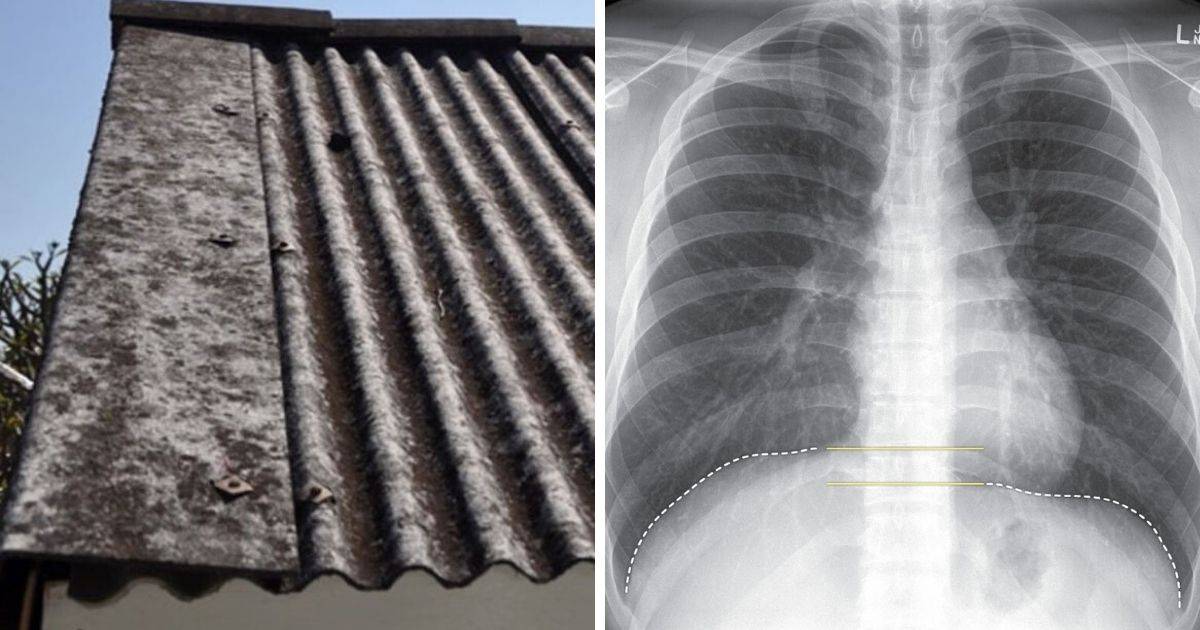

Berkongsi pengalaman menjaga pesakit kanser, Remaja berkesempatan bertemu dengan Dato’ Hans Isaac yang pernah menjaga mendiang ibunya yang disahkan menghidap kanser paru-paru kira-kira 10 tahun yang lalu.